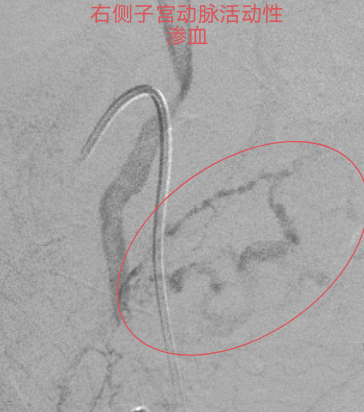

本着“生命至上”的原则,吴主任立即启动介入导管室为产妇施行“造影术”检查,造影发现产妇子宫动脉远端均有活动性出血,尤以左侧子宫动脉出血明显,血液不断外渗,病情紧急,止血治疗迫在眉睫!要知道产后大出血是非常凶险的疾病,不能有效止血可能需要切除子宫保命的!但患者才不到三十岁呀,正值青春年华,切除子宫对患者以后可是有非常大的影响。此时,能及时止血救命,又能保住子宫的微创介入止血法的优势就出来了!在患者及其家属的期盼和高度信任下,吴主任顺利为患者施行微创介入止血手术,术后患者子宫动脉出血停止,阴道出血减少,术后无需继续输血血压、血红蛋白均能维持稳定。术后经常规产后康复护理治疗后,患者病情稳定,没有异常阴道出血,现已康复出院。

血管造影见

双侧子宫动脉出血